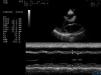

Physical examination revealed blood pressure of 130/90mmHg, heart rate of 122/min, a dilated jugular vein, and an audible gallop rhythm and systolic ejection murmur. There was mild peripheral edema. Chest radiography showed an enlarged and globular cardiac silhouette and pulmonary congestion without pleural effusion (Fig. 1). Serum free T3, T4, total T3, T4 and thyroid stimulating hormone (TSH) were within normal values with levothyroxine replacement therapy at a dose of 50μg daily. Cardiac enzymes, liver enzymes, erythrocyte sedimentation rate and C reactive protein were normal. Antinuclear, antithyroperoxidase and antithyroglobulin antibodies were positive. Rheumatoid factor and anti-α-myosin antibodies were absent. Coxsackie virus, Chlamydia pneumoniae and Mycoplasma pneumoniae serology were negative. Echocardiography showed decreased left ventricular systolic function with an ejection fraction (EF) of 32% and fractional shortening (FS) of 15%, as well as dilated left ventricle with decreased wall motion of entire left ventricle (Fig. 2). Dilated cardiomyopathy and hypothyroidism secondary to Peg IFNα-2a was suspected. Therefore, Peg IFN-α and ribavirin was discontinued after 23 weeks of treatment. The patient was treated with Benazepril, Digoxin, Furosemide, Metoprolol Succinate and Levothyroxine. Her symptoms improved in one week and she was discharged on the same medications. A second echocardiogram three months later showed an EF of 47% with normal chambers, and heart failure medications were discontinued. She maintained normal aminotransferases and undetectable HCV RNA after 24 months of follow up. However, she needs permanent thyroid hormone replacement therapy for hypothyroidism.